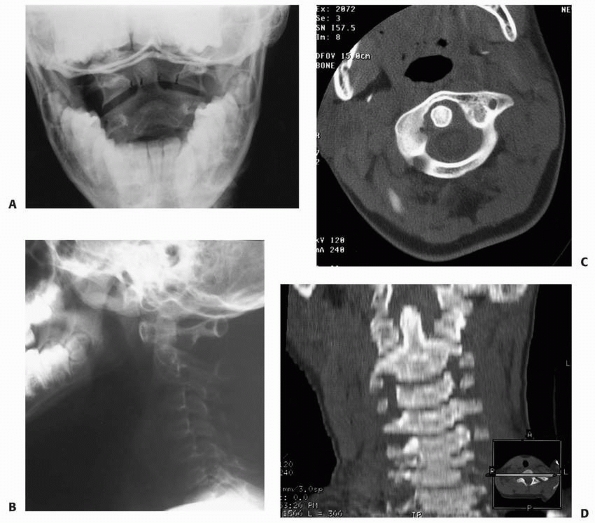

Plain radiographs often do not clearly show occipital condylar

fractures, and CT with multiplanar reconstruction usually is necessary

to establish the diagnosis.14,42 Tuli et al.225

recommended that a CT scan be obtained in the following circumstances:

presence of lower cranial nerve deficits, associated head injury or

basal skull fracture, or persistent neck pain despite normal

radiographs. Reports of associated cranial nerve deficits vary from 53%

to 31% of patients with occipital condylar fractures.9,92,225 Anderson and Montesano9 described three types of occipital condylar fractures (Table 18-2, Fig. 18-19):

type I, impaction fracture; type II, basilar skull fracture extending

into the condyle; and type III, avulsion fractures. An avulsion

fracture is the only type of occipital condylar fracture that is

unstable. Type I injuries are the result of axial compression with a

component of ipsilateral flexion. Type II injuries are basilar skull

fractures that extend to involve the occipital condyle and usually are

caused by a direct blow. Type III injuries are avulsion fractures of

the inferomedial portion of the condyle that is attached to the alar

ligament. Types I and II occipital condylar fractures usually are

stable and can be treated with a cervical orthosis. Type III or

avulsion fractures can be unstable and may require halo immobilization

or occipitocervical arthrodesis.6